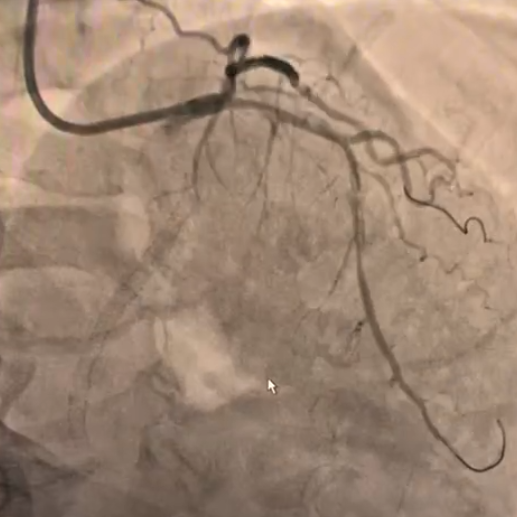

冠脉造影:前降支弥漫性病变,近段与间隔支形成分叉病变,最窄可见约90%狭窄。回旋支近段70%狭窄,远段弥漫性病变,最重处95%狭窄,远端可见侧枝向PDA供血。

预扩后IVUS检查:1.0-1.5球囊对OM2病变部位预扩后,狭窄无明显改善,IVUS提示钙化明显。

冲击波治疗:根据IVUS影像指导,使用2.5×12mm 国产冲击波球囊进行4个周期的治疗,复查造影提示狭窄减轻。

支架植入:在IVUS引导下,于OM2-LCX远端精准植入2.5×38mm药物支架,经非顺应性球囊后扩,术后造影及腔内影像确认支架贴壁理想,无边缘夹层及壁内血肿,TIMI血流3级。

冠脉造影:前降支近段80%、中段90%狭窄,第一对角支近段70%狭窄,回旋支近段70%狭窄,第一钝缘支90%狭窄。

IVUS检查:提示LAD近中段钙化病变伴360°环形钙化,狭窄最重处90%。2.0-2.5球囊逐级扩张后,支架无法通过。

冲击波治疗:使用2.5×12mm、3.0×12mm 国产冲击波球囊进多次预处理LAD近中段病变。

支架植入:串联植入2枚3.5×28mm/3.0×33mm支架覆盖LAD近中段钙化病变,通过IVUS实时优化后扩策略(序贯20/22atm高压扩张),最终支架膨胀、贴壁满意。